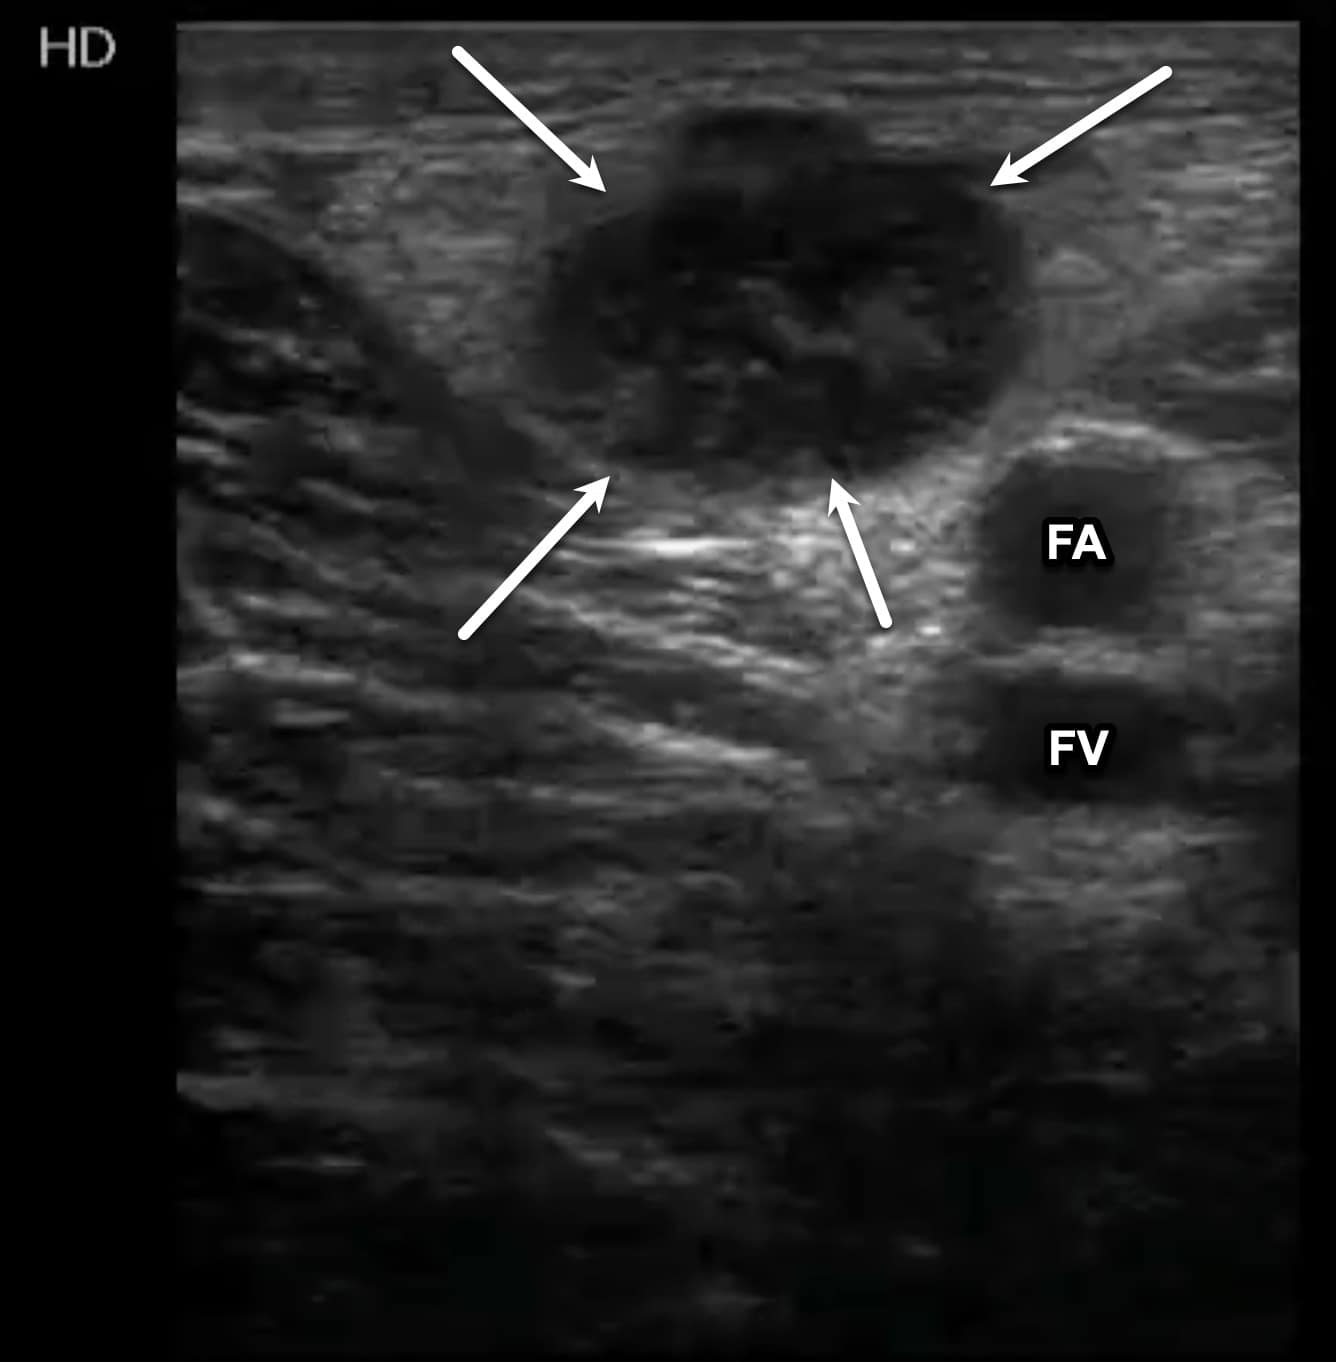

Once at the CFV/FV junction, it is important to look for evidence of venous duplication. Venous duplication occurs in a significant number of patients and is seen most commonly in the region of the FV and PV (Figure 7). Failure to identify venous duplication could lead to missing a DVT that occurs in only one of the systems. The FA is seen anterior to the FV in this region (Figure 8). As the FV approaches the adductor canal, an anterior approach utilizing an increased field of depth can also be used to better visualize the vein. Compression at this level is done by placing the freehand posteriorly and squeezing since transducer pressure will not result in venous compression with this approach (Figure 9).

Figure 7. Transverse window at level of left femoral vein (FV) with duplication noted. Note that one branch is medial to the femoral artery (FA) and the other is posterior.

Structures, such as lymph nodes or nerves, can be confused with a DVT. However, lymph nodes will be a fixed length and not associated with an adjacent artery (Figure 15). Nerves will often appear as cylindrical, hyperechoic structures with the characteristic “honeycomb” appearance. Baker’s cysts can also be seen during performance of this examination while evaluating the PV. These cysts are located between the medial head of the gastrocnemius and semimembranosus tendons and may be anechoic or echogenic with a characteristic beak-like appearance on sagittal imaging, but notably will not exhibit blood flow within (Figure 16).

Figure 15. Transverse window of an enlarged inguinal lymph node (arrows). The lymph node has an echogenic, circular appearance like that of a deep vein thrombosis (DVT). The femoral artery (FA) and femoral vein (FV) can be seen deep to the lymph node.